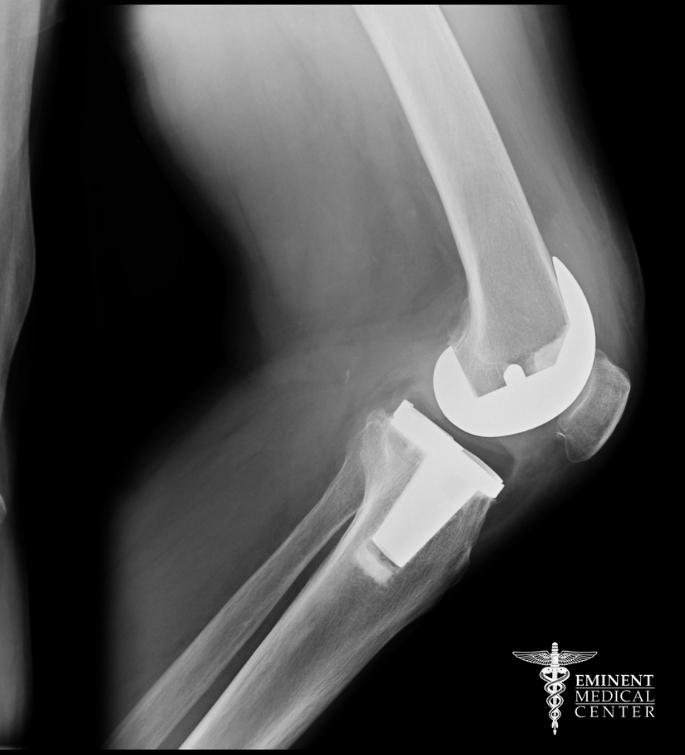

Knee Revision Surgery

Revision knee surgery, also known as revision knee replacement or revision total knee arthroplasty, is performed when a total knee replacement no longer provides adequate function or comfort. Causes for this procedure may include knee instability, wear of the plastic liner, excessive scar tissue, or loosening of the existing implant.

The revision typically involves removing old components, preparing bone surfaces, and implanting more durable parts. If the patient has significant bone loss, surgeons may use specialized implants or bone grafts.

If your knee replacement has failed or no longer provides relief, Eminent Medical Center offers advanced solutions, including MAKO total knee replacement in Richardson and Dallas. This cutting-edge technology allows for greater precision and a more personalized fit, helping you get back to moving comfortably and confidently.